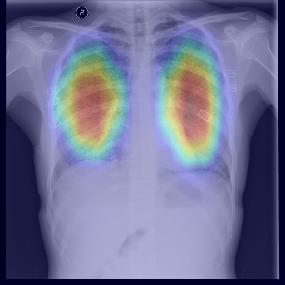

Chest X-ray (CXR) is the most typical diagnostic X-ray examination for screening various thoracic diseases. Automatically localizing lesions from CXR is promising for alleviating radiologists' reading burden. However, CXR datasets are often with massive image-level annotations and scarce lesion-level annotations, and more often, without annotations. Thus far, unifying different supervision granularities to develop thoracic disease detection algorithms has not been comprehensively addressed. In this paper, we present OXnet, the first deep omni-supervised thoracic disease detection network to our best knowledge that uses as much available supervision as possible for CXR diagnosis. We first introduce supervised learning via a one-stage detection model. Then, we inject a global classification head to the detection model and propose dual attention alignment to guide the global gradient to the local detection branch, which enables learning lesion detection from image-level annotations. We also impose intra-class compactness and inter-class separability with global prototype alignment to further enhance the global information learning. Moreover, we leverage a soft focal loss to distill the soft pseudo-labels of unlabeled data generated by a teacher model. Extensive experiments on a large-scale chest X-ray dataset show the proposed OXnet outperforms competitive methods with significant margins. Further, we investigate omni-supervision under various annotation granularities and corroborate OXnet is a promising choice to mitigate the plight of annotation shortage for medical image diagnosis.